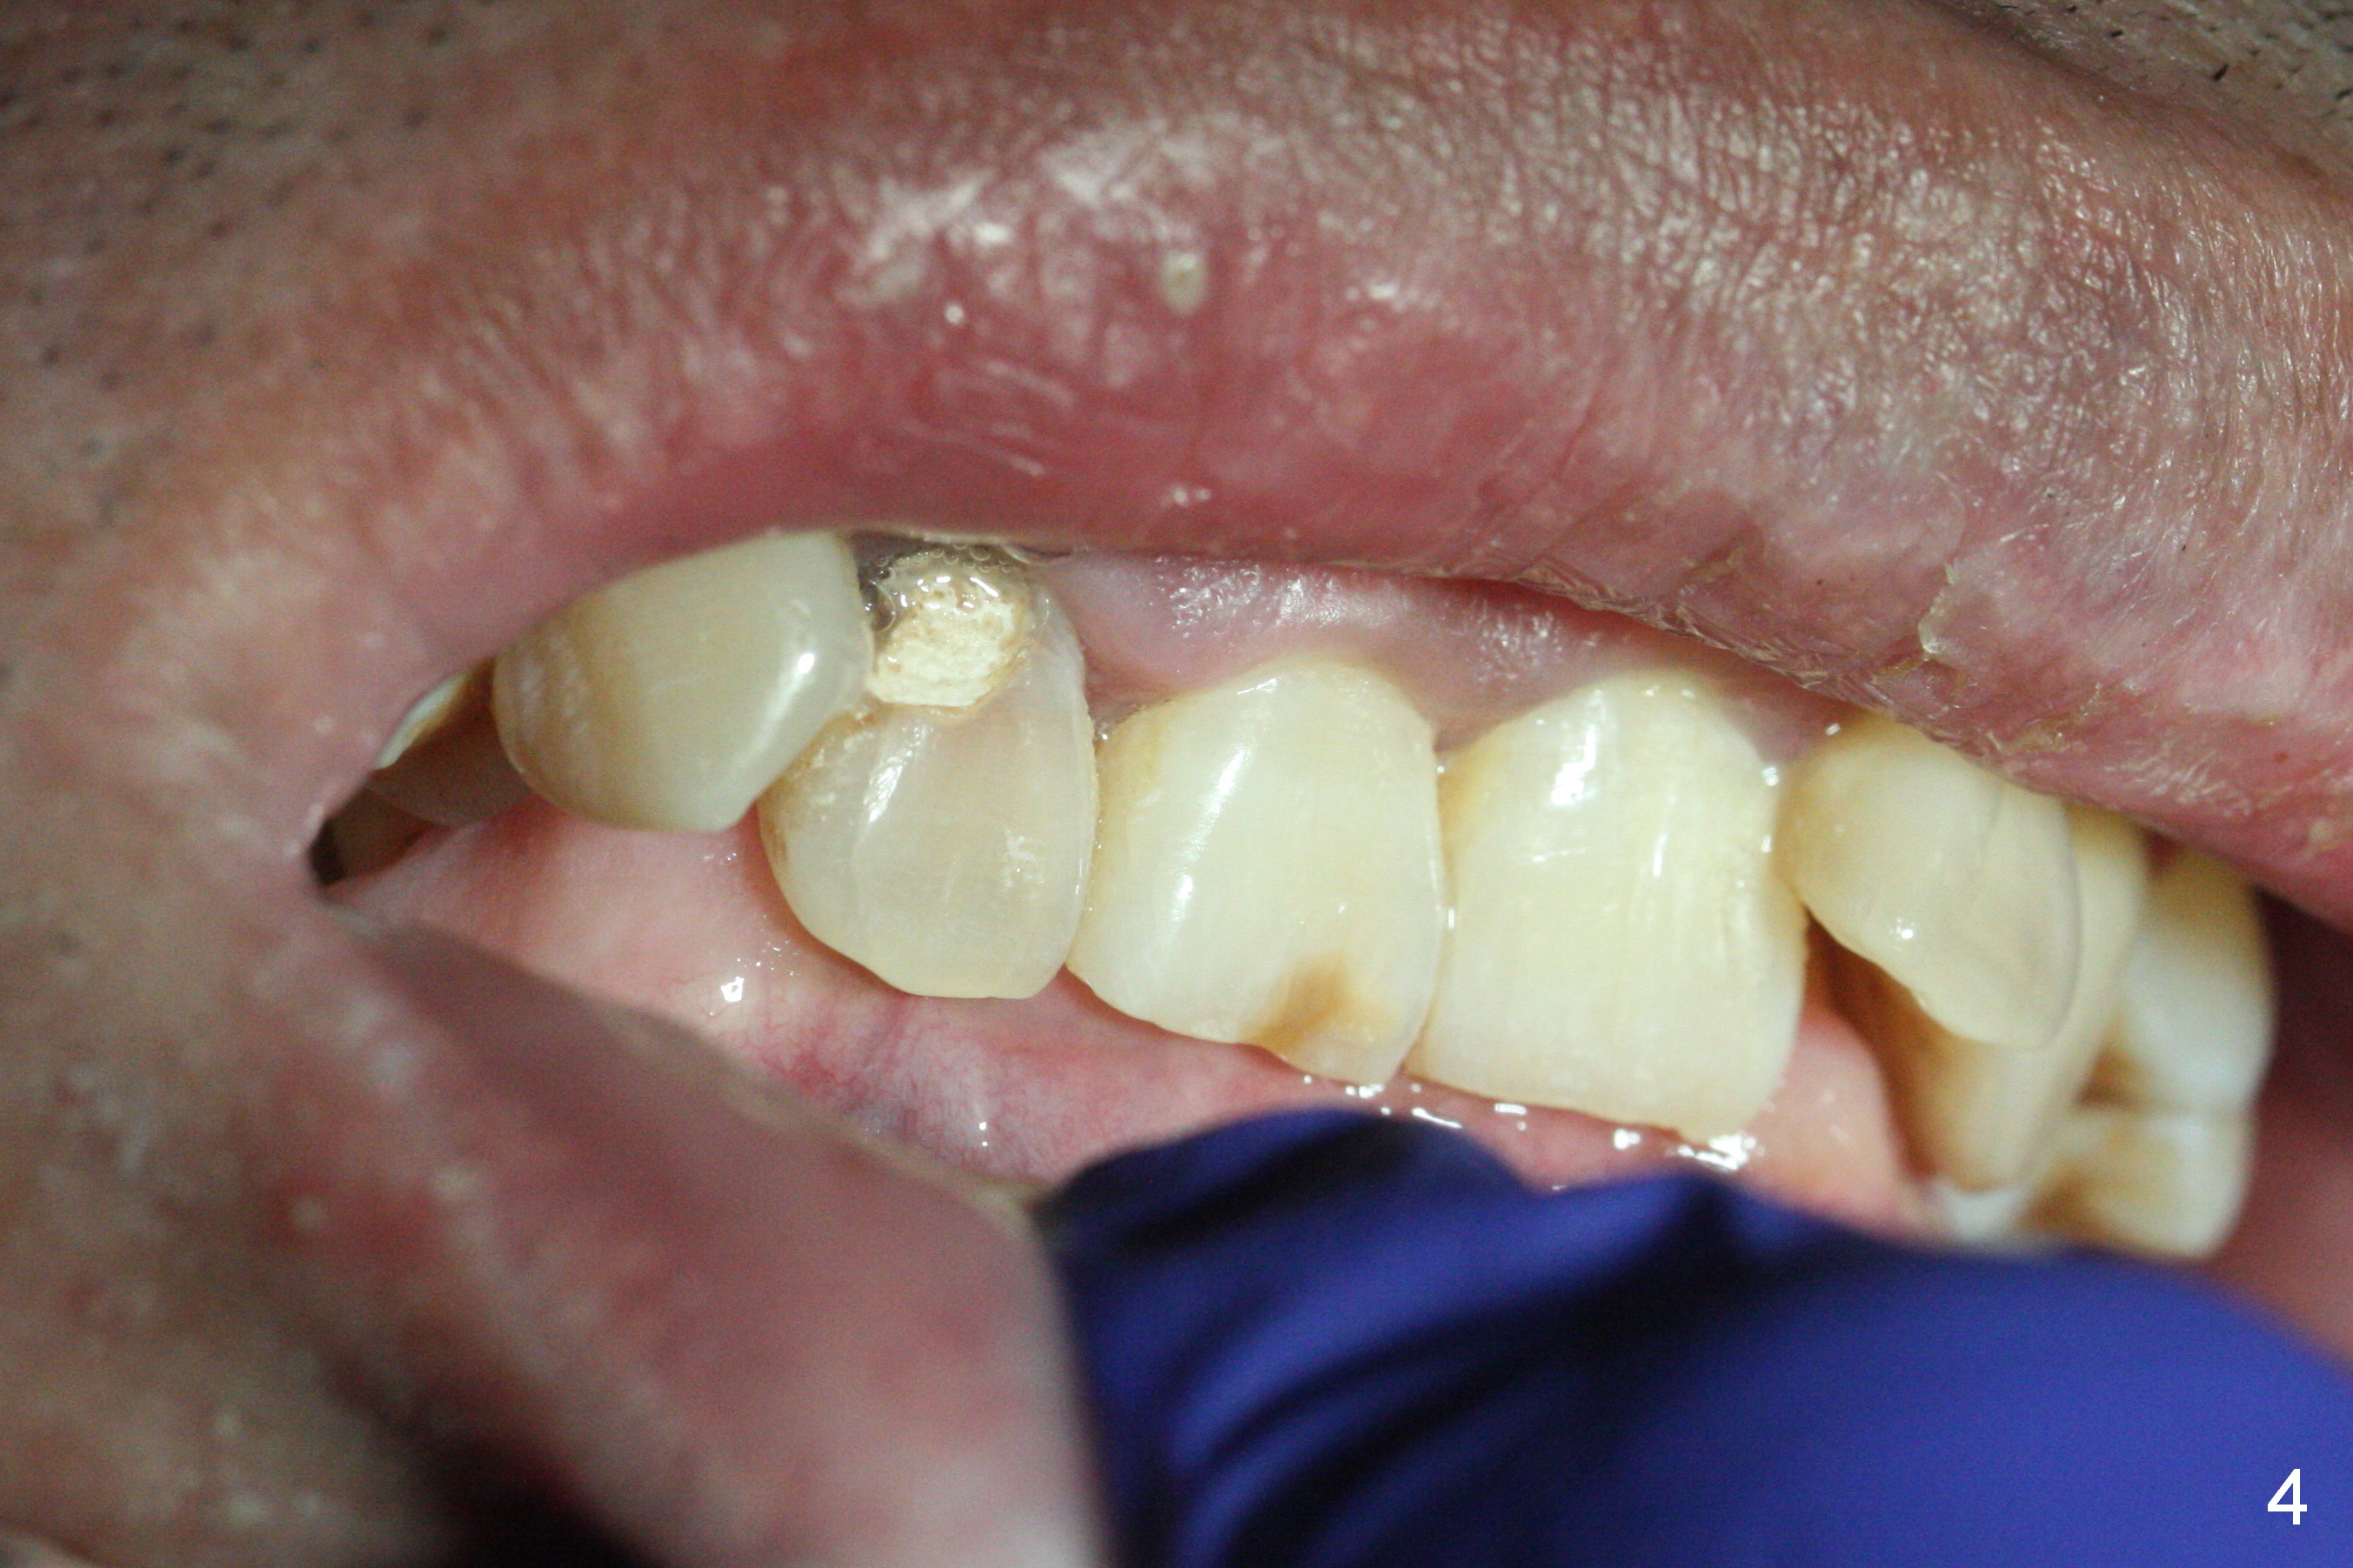

A 52-year-old man had a non-restorable lateral incisor 3 years ago (Fig.1). It fractures lately (Fig.2) with a buccal abscess (Fig.3 *) ) and fistula (>, possible severe buccal plate defect, prepare PRF). Severe deep bite (Fig.4) and malocclusion (Fig.5) will present a challenge to implant provisional restoration.